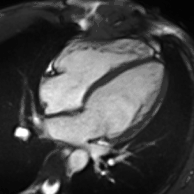

Late gadolinium enhancement

Gadolinium-based contrast agents are administered intravenously and delayed imaging is performed at least 10 minutes later to achieve optimum contrast between normal and infarcted myocardium. An inversion recovery (IR) sequence is used to null the signal from normal myocardium. Myocardial viability can be assessed by the degree of transmural enhancement. Cardiomyopathic, inflammatory and infiltrative diseases may also have distinctive patterns of non-ischemic LGE.[21][22]